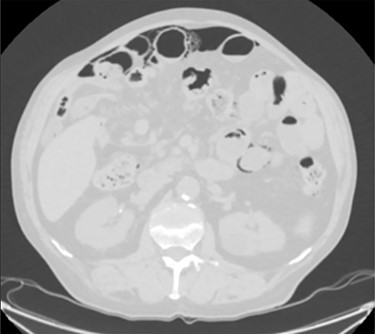

This is a case of a 79-year-old man who underwent contrast-enhanced Brain-CT for loss of consciousness. Past medical history included diverticular disease, COPD, hypertension, atrial fibrillation and appendectomy. Of note, he had no prior history of endoscopic procedures or recent trauma. The CT showed a primary cerebral mass at the temporal right site suspected for a glioblastoma. Hence, he went through a contrast-enhanced Chest/Abdomen CT for staging. No secondary lesions were detected but a small amount of free gas was unexpectedly noted in the abdomen secondary to a suspected colonic diverticular perforation (Fig. 1). Therefore, a surgical consultation was granted. At a first observation the patient was totally asymptomatic. Vital signs were in range. He had a healthy appetite, bowel sounds were active and he was opening his bowels normally. On examination the abdomen was soft and nontender with no distension. Laboratory tests were also normal including WCC (4.72 × 103/μl) and CRP (2.05 mg/dl). To confirm the diagnosis we proposed an explorative laparoscopy that the patient refused as he was feeling well. Few weeks later he underwent neurosurgical intervention and the cerebral mass was resected. The postoperative period was uneventful and he was discharged home on postoperative Day 7.

A moderate amount of intraperitoneal gas is present anteriorly to the small bowel.